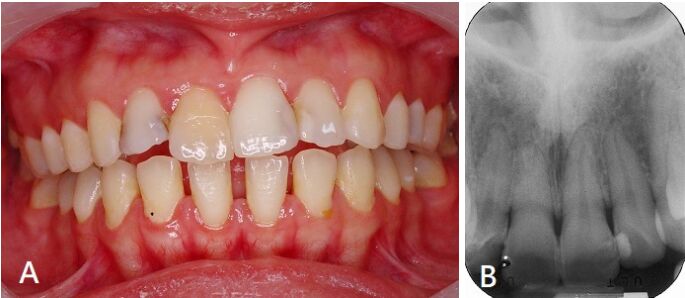

9.如圖,25歲男性於數年前右上門牙曾撞到,當時除疼痛外無其他症狀,也未曾就醫,目前檢查並無臨床任何症狀,電髓活性測試為無反應,有如圖A之變色,X光顯示如圖B。關於tooth 11,下列敘述何者正確? (A)牙髓產生鈣化現象,若無症狀,觀察即可 (B)應進行窩洞測試(test cavity)以確認牙髓活性 (C)需進行根管治療,以預防日後根尖病灶的形成 (D)牙髓在當時外傷應已壞死,只是未發生感染,觀察即可